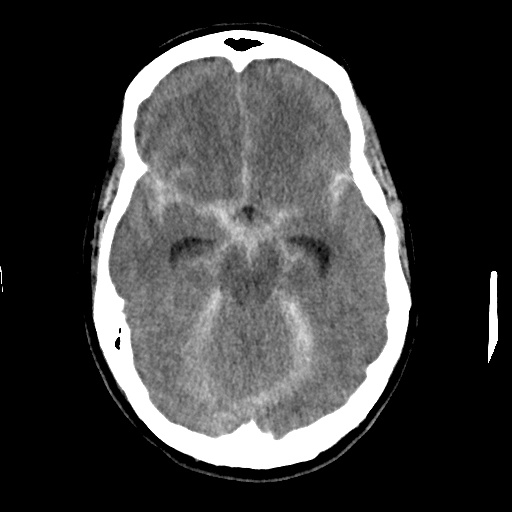

The ambulance took me to a local hospital where shortly after I arrived I became unresponsive and my heart stopped beating; I went into cardiac arrest. I was successfully resuscitated and intubated. A CT scan of my brain showed massive and diffuse subarachnoid hemorrhage.

I was then flown to UMass Hospital, where on

arrival I remained unresponsive and another CT scan of my brain showed that the bleeding was getting worse. It showed an evidence of obstruction of the spinal fluid (CSF) drainage system by the blood causing increased pressure in my head. A neurosurgeon placed an EVD (Extra-Ventricular Device) to drain the blood and the CSF and relieve the pressure, right after that I underwent a cerebral angiogram procedure (similar to a heart cath as a technique but it images and intervenes on the brain arteries instead), they found a 3.2 mm x 3.4 mm aneurysm in the left side of my brain outpouching off an artery called the left posterior communicating artery (PComm.), the aneurysm was successfully coiled. While in the angiography suite, my blood pressure dropped and the oxygen level dropped too. They had to put me on vasopressors to raise my blood pressure. I was having large amounts of frothy secretions coming out of my airways. A central venous catheter was placed in my right internal jugular vein emergently and another catheter was placed in my femoral artery to monitor my blood pressure. An echo of my heart showed a weakened muscle pumping only 15% (normal is ≥ 55%). I was then in the Neurological Intensive Care Unit for three weeks. My blood pressure continued to drop and I was again on more medications to raise my blood pressure. My heart enzymes have already started to increase and the echocardiogram showed a globally reduced contraction consistent with stress-induced cardiomyopathy or what is referred to sometimes as “broken heart syndrome”, but it won’t give up on me nor would the doctors and the staff in the NeuroICU. My blood pressure continued to drop and more IV medications to raise it couldn’t do the job, the other organs in my body weren’t getting enough blood supply or oxygen. They called a cardiac surgeon who placed an intra-aortic balloon pump to take off some of the load on my heart and augment blood supply to my organs. Within 48 hours I was successfully weaned off the intra-aortic balloon pump.

I was already put on medications to prevent seizure and on antibiotics to treat pneumonia. The pressure in my head was rising threatening my brain to herniate, but I was treated successfully for that. My legs stopped moving, and a Doppler ultrasound of the brain vessels showed diffuse constriction of the arteries referred to as vasospasm, yet another complication of the subarachnoid hemorrhage, and I again underwent cerebral angiogram where a medication infused in the brain arteries to successfully relieve that vasospasm. A CT scan and MRI of the brain showed multiple areas of stroke in my brain, but none affecting my language center or motor control areas. After that it was a matter of time to start improving with the extraordinary care from the team of doctors, nurses and other staff in the Neuro ICU. I left after three weeks of a miraculous journey to continue recovering in a rehabilitation center.